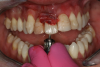

The next case follows the digital protocol for fully guided surgery and prosthetics. A CBCT radiograph, digital impression, and digital photography were the cornerstones to the success of this case. The 3D data set was electronically delivered to the dental laboratory. The data were merged and the process to develop the plan was initiated. The use of CBCT was essential in this case, particularly due to minimal space for placement of individual implants and single-unit crowns. The patient's chief concern was that she wanted to have single-unit crowns instead of fixed crown-and-bridge restorations because she was worried that she would someday find herself in an assisted-living facility; if that were to happen, she wondered, who would help floss under her bridge work? Her decision was to have single implants with individual crowns. CBCT technology is much more accurate in evaluating space maintenance and management.10 Periapicals in the past were rather close for calculating spacing; however, the CBCT identifies the buccal-lingual dimensions as well as the mesial-distal measurements. On review of the completed proposals for implant placement and provisionals, it was determined that there was sufficient spacing for implant placement to allow appropriate emergence profiles for the provisionals and then eventually the final single-unit cemented crowns. The proposal was accepted, and a 3D-printed surgical stent was fabricated, along with the PMMA provisionals (Figure 29 through Figure 35).

Fig 36. Anterior central view.

Figure 36

Fig 37. Pontic removal of No. 23 and teeth extractions.

Figure 37

Fig 38. Periodontal casualties.

Figure 38